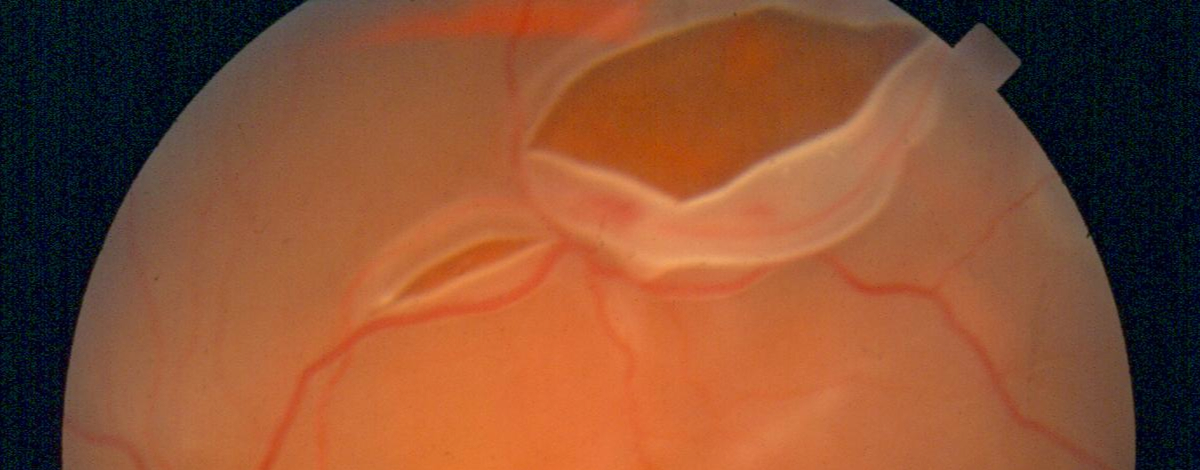

Vitrectomia

In casi eccezionali si può ricorrere alla vitrectomia per rimuovere gli aggregati vitreali